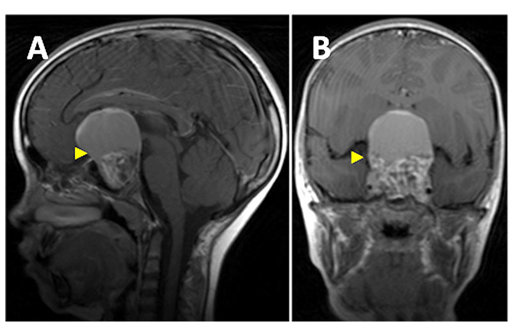

U sọ hầu là một trong những căn bệnh hiếm gặp là thuộc dạng u lành tính, thường hình thành ở trẻ nhỏ. Với tốc độ phát triển khá chậm và đặc điểm lành tính, khối u sẽ không gây hại đối với sức khỏe người bệnh. Tuy nhiên, mọi người không nên chủ quan, nếu phát hiện khối u chúng ta nên theo dõi và đ...